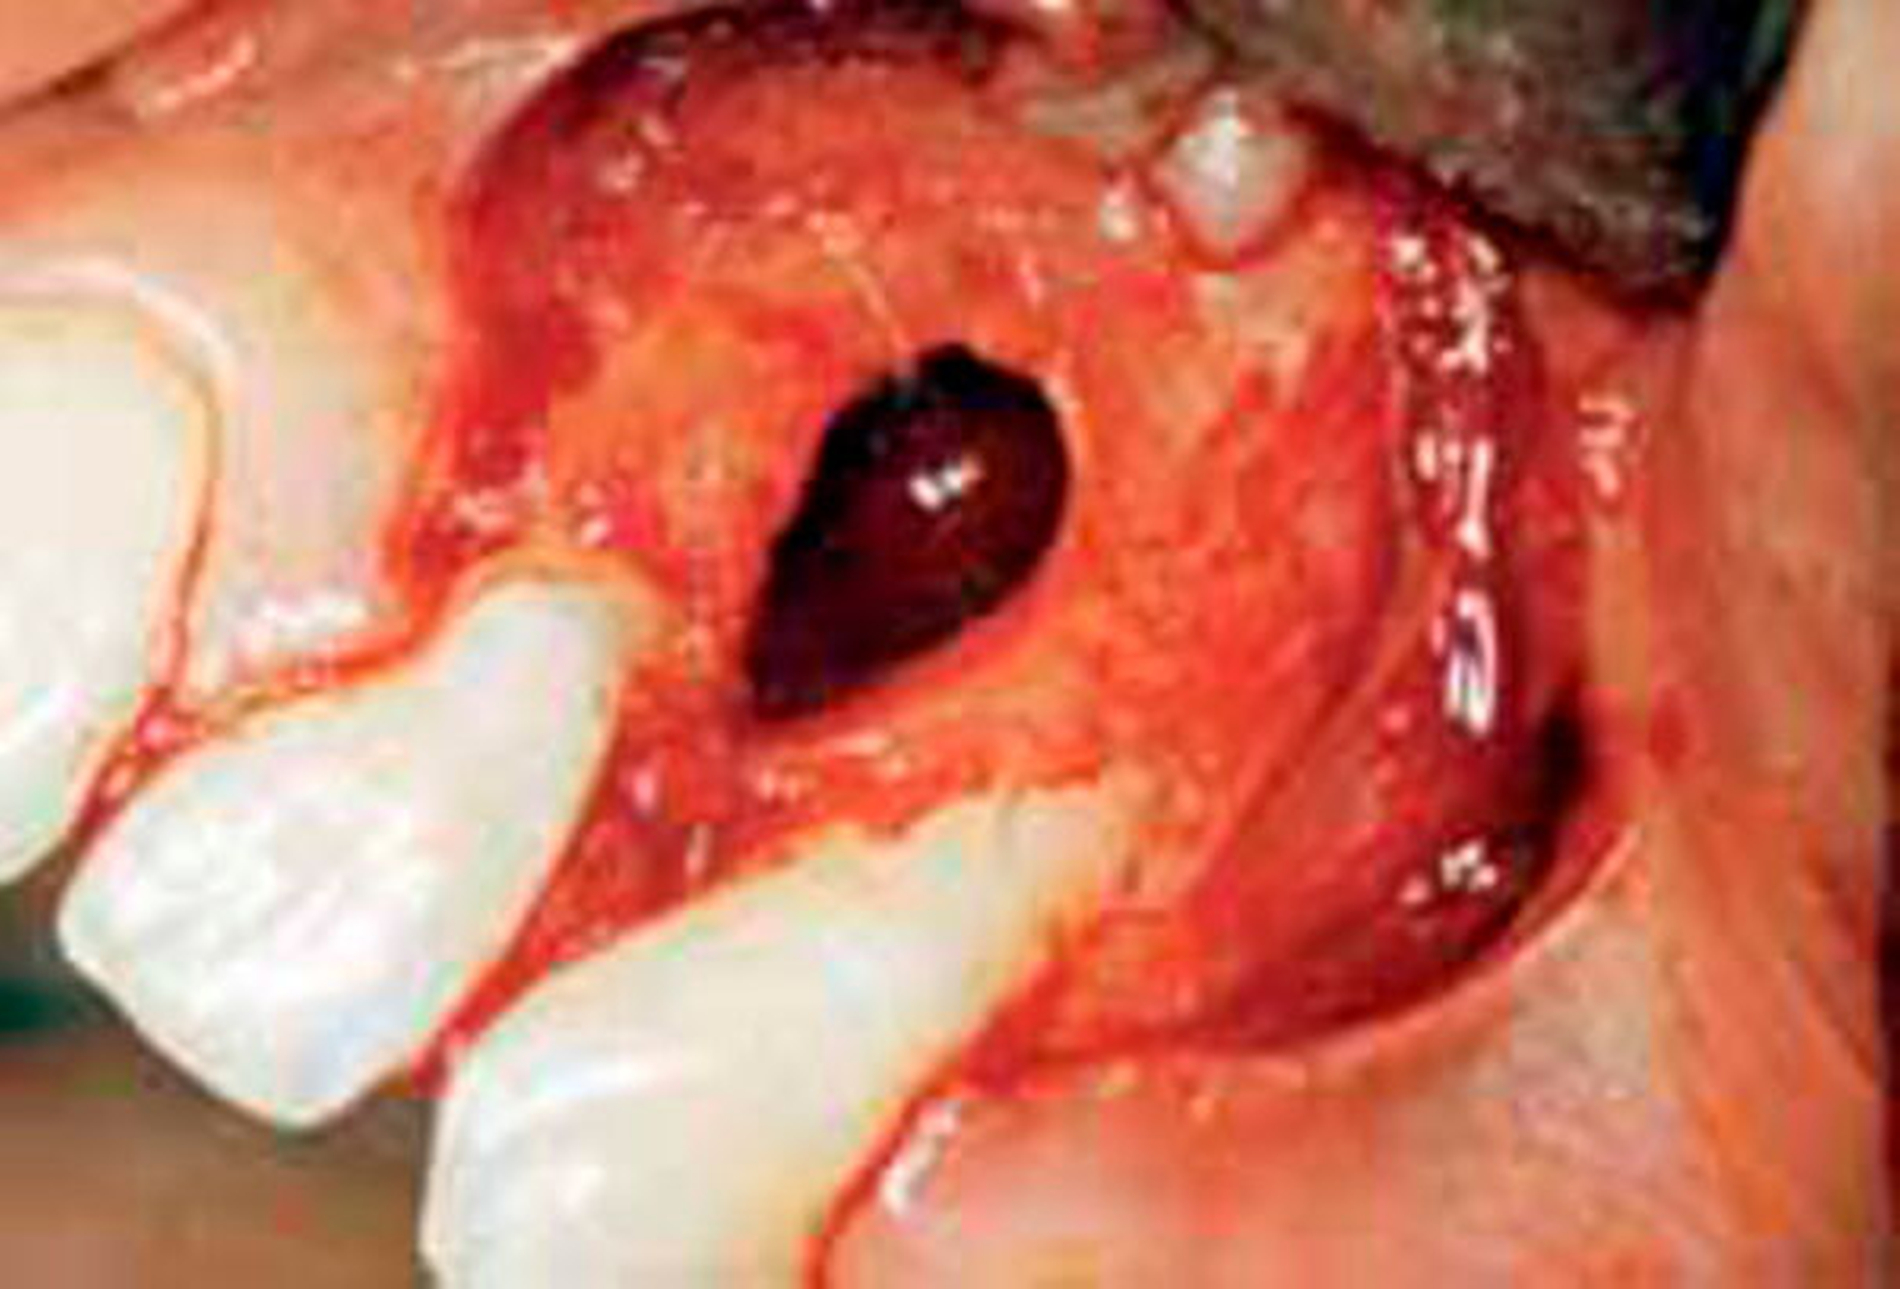

Die GZ wurde auch der parodontalen Zyste gegenübergestellt. Während letztere zwischen den Wurzeln sämtlicher Zähne entstehen kann, erscheint die GZ typischerweise nur zwischen dem lateralen Schneidezahn und dem Eckzahn, dort wo sich Prämaxilla und Maxilla vereinen. Es wurde Wert darauf gelegt, dass die Zyste zwischen parodontal und pulpal gesunden Zähnen vorkommt und somit ein Zweifel an ihrem fissuralen Ursprung ausgeschlossen ist. Die GZ verdrängt die Wurzeln des lateralen Incisivus und des Eckzahns, was als erstes klinisches Zeichen beschrieben wird. Später kann es zu einer Vorwölbung der vestibulären Schleimhaut kommen, oft assoziiert mit einem Druckgefühl (Abb. 1 bis 5).

In einer weiteren Untersuchung wurden acht Zysten in der globulomaxillären Region gefunden, welche die klinischen und histologischen Kriterien für eine IPC erfüllten [Vedtofte & Holmstrup, 1989]. Das Durchschnittsalter der Patienten betrug 18,8 Jahre. Die Nachbarzähne waren immer vollständig eruptiert. Dreimal gab es eine Verbindung zwischen Zyste und Parodontaltasche, während in den verbleibenden fünf Fällen keine Kommunikation gefunden wurde. Bei fünf Patienten waren die IPC asymptomatisch und wurden zufällig radiologisch diagnostiziert. Drei Patienten zeigten Symptome einer akuten Infektion. Radiologisch präsentierten sich die Zysten als klassische GZ. Die Größe der Zysten variierte zwischen 14 x 10 Millimeter bis 23 x 14 Millimeter. Die pathohistologische Auswertung ergab, dass alle Zysten durch ein hyperplastisches, nicht keratinisiertes, mehrschichtiges Plattenepithel begrenzt wurden. Das darunter liegende Bindegewebe präsentierte sich in allen Fällen mit einer starken entzündlichen Infiltration. Postoperativ reossifizierte der knöcherne Defekt immer problemlos; die Nachbarzähne blieben vital [Vedtofte & Holmstrup, 1989].

Die klinische und pathohistologische Evidenz spricht überzeugend dafür, dass Zysten im „Globulomaxillären Bereich“ radikuläre Zysten, laterale Parodontalzysten, odontogene Keratozysten [Christ, 1970], kalzifizierende odontogene Zysten, adenomatoide odontogene Tumore [Rosenberg & Cruz, 1963; Giansanti et al., 1970; Khan et al., 1977], odontogene Myxome [Rud, 1964; Taicher & Azaz, 1977], Ameloblastome [Aisenberg & Inman, 1960], zentrale Riesenzellgranulome oder hämorrhagische Knochenzysten [Peters & Wassow, 1968] sind (Abb. 6 bis 13).